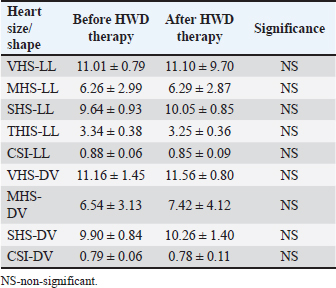

Cardiac size and shape assessed by calculated modified VHS, MHS, SHS, TIHS, and CSI, both in LL and DV radiographs, did not differ significantly before and after HWD therapy (Table 6). Table 6. Objective heart size/shape measurements before and after therapy in the dogs with HWD.

DiscussionThoracic radiography is a widely available diagnostic method used for the evaluation of cardiovascular and respiratory organ systems in small animal practice. In spite of its limitations, it is still used to assess the heart, blood vessels, and lung field. Interpreting dog radiographs can be challenging not only because of the wide variety of thoracic shapes and sizes in different breeds, but also due to positioning and technique. Furthermore, the numerous described radiographic methods for assessing heart size and shape [intercostal spaces, VHS, heart to single vertebra ratio (HSVR), MHS, SHS, TIHS, CSI, cardiothoracic ratio, tracheal-bifurcation angle, vertebral left atrial size, modified vertebral left atrial size, radiographic left atrial dimension, radiographic left atrial dimension to spine, bronchus to spine] seem to contribute to interpretation complexity. In the present study, radiographic methods relevant for the assessment of HWD characteristics were applied on radiographs of dogs with HWD in order to test their feasibility and determine their results. In clinical practice, diagnostic methods that are accurate, easy to perform, and no time consuming are the preferable ones. By comparing different methods on the same radiograph, it is possible to find out which diagnostic methods have higher potential over others in terms of feasibility. However, as this study shows, it is possible that in some patients more accurate and objective radiographic methods are inferior to others. Therefore, a holistic approach that includes both subjective and objective methods is required in interpreting dog radiographs. Subjective radiographic methods could be used in all dogs, while none of the applied objective methods could be used in two dogs, which had the most severe radiographic changes. Abnormal lung field, in the sense of massive opacities throughout several lung lobes, was the reason that prevented the assessment of the cardiac silhouette and blood vessels in these two dogs. Such changes raised suspicions about the existence of PTE, one of the most severe HWD complications. Subjective parameters of cardiomegaly, and even more so of abnormal lung patterns, could be assessed in the majority of dogs. However, the impossibility of assessing certain subjective parameters, even the most prevalent ones in the dogs with HWD, such as the size of the RCaLA in comparison to that of the corresponding vein, was observed. Pathological changes in the lung field, and incorrect positioning of the patient were mostly the reasons. Among the objective methods for the determination of cardiac size and shape, the most feasible ones were modified VHS, SHS, and CSI (in 38 out of 40 dogs for LL view, and 32 out of 36 dogs for DV view). The determination of cardiac size by MHS and TIHS was possible in only a smaller number of the dogs (in 23 and 26 dogs, respectively). While pathological lung changes prevented the determination of modified VHS, SHS, and CSI, particularly in DV radiographic view, the incorrect positioning of the dog and unsuccessful determination of the cranial M margin were the reasons for the impossibility of MHS and TIHS measurements. The assessment of the blood vessels relevant for HWD was most feasible for the RCrLA, followed by the VCC and the RCaLA, both for subjective and objective methods. In the case of the RCrLA, detection was possible in 36 dogs, both for the subjective method, in which it was compared with the corresponding vein, and for the objective methods, in which its width was expressed in mm, or as a ratio to the T4. It was possible to assess the VCC in comparison to the Ao, either subjectively or objectively, only in 17 dogs. However, it was more feasible to assess the VCC by direct measurement or indirectly as a ratio to the T4 (in 30 dogs) or to the 4.r (in 33 dogs). In the present study, objective methods of cardiac size and shape measurements were done as previously described (Guglielmini et al., 2012; Mostafa and Berry, 2017; Marbella Fernández et al., 2023a), with the exception of VHS, in which case the modified VHS was used. We have previously proved that no significant differences exist between heart size measured by the original VHS and the modified VHS methods in healthy dogs of the same breed (Spasojević Kosić et al., 2007), and in dogs with HWD of different breeds (Spasojević Kosić and Lalošević, 2025). Recently, the comparison of the cardiac axes with a single thoracic vertebra was also introduced as an objective method of evaluation of the cardiac silhouette (Costanza et al., 2022). The most accurate way of measurement in this, so-called, heart to single vertebra ratio (HSVR) is when the cardiac axes sum is compared with the length of the seventh thoracic vertebra (T7). Besides T7, other thoracic vertebrae can be used in the following order of preference T8, T5, T6, and, at the end T4, as it shows the lowest, although still acceptable level of agreement with VHS (Costanza et al, 2022). In our study, we used T4, not just because of the lack of significant difference from the original VHS method, but because of the uniformity of the measurements, since the blood vessels dimensions were also presented in this manner. We have found a very strong correlation between T4 and S4 (r=0.91, p < 0.05), and also significant but lower correlation between T4 and M (0.86, p < 0.05), and M and S4 (0.84, p < 0.05). However, there were no significant correlations between any of these skeletal structures and TI. This is opposite to the significant correlation found between TI and T4 in the study by Marbella Fernández et al. (2023a). In the study of Buchanan and Bücheler (1995), good correlations were detected between the LA dimension, SA dimension, and the sum of LA and SA dimensions and the 10 v reference length, as well as between heart size and the length of 3 or 4 sternebrae. Similarly, significant correlations were detected between cardiac LA, SA, the sum of the LA and SA, and the M length (Mostafa and Berry, 2017). These findings are in accordance with significant correlations, from very strong to moderate, detected in the present study between LA, SA, the sum of LA and SA, and each of the skeletal units (T4, S4, TI, M). In the study of Buchanan and Bücheler (1995), the M was excluded because of its variability, and the sternal measurements extended from the cranial edge of the second sternebra to the caudal edge of the fourth and fifth sternebrae were done. The purpose of the sternal measurement was to determine whether sternal length is more reliable than vertebral length as an index correlate for the heart size. As sternebral correlations were slightly less than vertebral correlations, no advantages of such measurement were seen, except in dogs with vertebral anomalies. In spite of these findings in dogs, and similar ones in cats (Litster and Buchanan, 2000; Ghadiri et al., 2008), sternebral heart score was not introduced as a method for heart size assessment until the recent study in ferrets (Gutiérrez et al., 2022). In accordance with the modified VHS method, the original SHS method (Gutiérrez et al., 2022) is modified in the present study, and a single sternebra, the S4 is used as a skeletal unit. In addition, a pronounced sternum arch in certain dogs due to chest conformation made it impossible to perform the measurement along the sternum. It was not difficult to perform this method, and it was equally feasible in the dogs with HWD as the modified VHS. Also, there were very strong and strong correlations between the S4 and the T4, and the S4 and heart size. Thus, the SHS method might be a useful method for evaluating heart size in dogs. However, the accuracy of each novel method of measurement should be estimated in comparison with gold standard methods, and its reproducibility should be tested so that an operator’s experience has a minimum impact on the results. Finally, reference values of measurement in healthy dogs should be defined. The subjective parameters of cardiomegaly, such as the increased sternal contact (91.89%), reversed “D” shape of the heart (89.65%), vascular patterns, such as the RCaLA enlargement (86.67%), and the loss of margination of pulmonary vessels (84.21%) were the most prevalent subjective radiographic parameters in the dogs with HWD. Similarly to our study, the reverse D shape of the heart, main pulmonary artery, and peripheral pulmonary artery dilation, as well as evidence of right heart failure were noted in the study by Kim et al. (2019). In another study (Maerz, 2020), enlarged peripheral pulmonary arteries were detected in the majority of dogs (65%), followed by parenchymal lesions (41%) and bulging of the main pulmonary artery (23.5%). In the study by Tudor et al. (2014), vascular radiographic changes (72.29%), pulmonary parenchymal changes (61.44%), and heart shape and silhouette changes (46.99%) dominated in the radiographs of dogs with HWD. Thrall and Calvert (1983) detected an enlarged right ventricle and RCaLA in every dog with HWD. These radiographic features were followed by pathological pulmonary abnormalities, enlarged RCrLA, main pulmonary artery, and VCC (Thrall and Calvert, 1983). Similar findings in dogs with HWD, such as the detection of right ventricular, main pulmonary, and RCrLA enlargement, were found by other authors (Losonsky et al., 1983). In the present study, pleural effusion was not detected in the dogs with HWD. The same result was reported in the study by Thrall and Calvert (1983), while Tudor et al. (2014) identified pleural effusions in 2.41% of dogs. Even though the parameters of cardiomegaly were more prevalent than the lung abnormality parameters, when radiographs before and after the HWD therapy were analyzed, no significant difference was found in the occurrence of the parameters of cardiomegaly, but among abnormal lung pattern parameters. After HWD therapy, the occurrence of main pulmonary artery enlargement in LL (p=0.0256; p ≤ 0.033, FDR), and the areas of increased opacity that tend to coalesce (p=0.0385; p ≤ 0.05, FDR) were significantly lower than before therapy. Thus, subjective radiographic assessment in the present study was able to register an improvement of lung pattern abnormalities, but not changes in cardiac size. In another study, radiographic features, such as increased pulmonary trunk, right atrial and ventricular enlargement, diffuse densification, and reticular interstitial lung patterning of the diaphragmatic lobes, became less frequent in the radiographs of the dogs after the therapy for HWD (Bendas et al., 2016). The only radiographic characteristic that was more frequent in dogs after the HWD therapy was increased diameter of the pulmonary arteries (Bendas et al., 2016). However, in the study of Bendas et al. (2016), the frequency of the radiographic features before and after the therapy, was expressed in absolute numbers without any statistical analysis. Cardiac size showed higher values in DV radiographs in all methods of objective measurement. In LL view, a heart size of 10.52 ± 0.97 v was measured by the modified VHS method, and in DV, the measured heart size was 10.79 ± 1.12 v. A similar value of VHS (10.59 ± 0.87 v in LL view) was measured in dogs of different breeds with HWD (Tudor et al., 2014). The value of VHS≤10.5 v is suggested as the clinically upper limit for normal heart size in most breeds (Buchanan and Bücheler, 1995). Despite the fact that thoracic radiography can underestimate the severity of HWD in small dogs, no significant difference was found between VHS in small and large breed dogs (Kim et al., 2019). Also, when values of VHS in LL and DV views were compared between dogs in different classes of HWD (classes 1–3), no significant difference was observed (Pajas and Acorda, 2018). When the M is used as a skeletal unit of cardiac size measurement, the mean value of 5.19 ± 1.80 was measured in LL radiographs in the present study. This value is similar to the value of MHS (5.2 ± 0.4) in large dogs with right-sided heart disease reported by other authors (Mostafa et al., 2020). More than overall MHS, the value of short MHS (the ratio of cardiac SA and the M length) is suggestive of right-sided heart disease (Mostafa et al., 2020). Known as a measure of cardiac shape, the CSI values of 0.86 ± 0.08 and 0.75 ± 0.07, in LL and DV views, respectively, were measured in the dogs with HWD in the present study. These values are lower than the CSI values of 88 ± 6.0 and 92 ± 8.0 measured in large and small dogs with right-sided heart disease (Mostafa et al., 2020), and in dogs with dirofilariasis belonging to various classes of HWD (Pajas and Acorda, 2018). By using TI as a skeletal unit, the heart size of 3.03 ± 0.41 was measured in LL radiographs of the dogs with HWD in the present study. This value is higher than the mean TIHS value of normal dogs (2.86 ± 0.27), but lower than the upper limit (3.2) of normal heart size in healthy dogs (Marbella Fernandez et al., 2023a). Although it is shown that a value of TIHS ≥ 3.3 can identify left heart enlargement in dogs with MMVD (Marbella Fernandez et al., 2023b), no studies on the subject of TIHS in right heart enlargement, right-sided heart disease, or HWD have been published yet. Values of 9.22 ± 1.04 and 9.49 ± 0.96 were measured by SHS in LL, and DV views, respectively. Since no values of SHS in healthy and diseased dogs have been published yet, it is not possible to compare this result with other studies. Similarly to the results of subjective radiographic assessment, no significant differences were detected between objective parameters of heart size and shape before and after therapy in the present study. However, another study shows that VHS has a tendency to increase after therapy for HWD in dogs with or without PH (Falcon Cordon et al., 2024b). In the study by Falcón Cordón et al. (2021), the RCrLA and the RCaLA expressed as a ratio to the ribs in dogs with HWD-induced PH were 1.4 ± 0.4 and 1.6 ± 0.6, respectively, while lower values (0.89 ± 0.25 for the RCrLA and 1.35 ± 0.40 for the RCaLA) were measured in the present study. There is a scarcity of reports about measurements of the pulmonary lobar arteries in HWD. On the other hand, several studies reported measurements of VCC. In dogs with dirofilariasis, classified in classes from 1 to 3, the VCC was measured as a ratio to Ao, T4, and 4.r (Pajas and Acorda, 2018). Our measurement of VCC/Ao (0.79 ± 0.20) was lower compared to the values in dogs in different classes of dirofilariasis (0.84 ± 0.11 – 1.02 ± 0.11) published by Pajas and Acorda (2018). The value of the VCC/T4 in our study (0.78 ± 0.15) was in the range of measured values in dogs in different stages of the disease (0.74 ± 0.07–0.81 ± 0.09) (Pajas and Acorda, 2018). However, the VCC/4.r in our study (2.58 ± 0.54) was higher than values reported in dogs in different classes of dirofilariasis (1.96 ± 0.21–2.25 ± 0.28) (Pajas and Acorda, 2018). Nonetheless, our measurements of the VCC (VCC/Ao, VCC/T4, VCC/4.r) were much lower than the values (VCC/Ao >1.50, VCC/T4 >1.30, VCC/4.r>3.50) reported for right sided heart abnormality by Lehmkuhl et al. (1997). Although observed, the diminishment of the relevant blood vessel diameters was not of statistical significance in the present study. The same findings for the lobar arteries were detected after HWD therapy in dogs without PH, but not in dogs with PH, where a significant increase in RCrLA/4.r and RCaLA/9.r ratios was observed after HWD therapy, indicating the persistence and worsening of the arterial damage (Falcon Cordon et al., 2024b). In this sense, it was concluded that RCrLA/4.r and RCaLA/9.r ratios, together with VHS, may be useful screening tools with which clinicians can decide whether to perform further diagnostic procedures, primarily echocardiography, to determine the presence of PH (Falcon Cordon et al., 2024a,b). Some limitations of the present study should also be addressed. The study design did not allow considerations of interobserver variability and interbreed variations for different radiographic methods. Due to the fact that SHS in normal healthy dogs has not been reported yet, it was not possible to compare the calculated value of SHS in the dogs with HWD. In addition, other diseases, mainly of cardiovascular and respiratory systems, which could influence or potentiate the radiographic features, were not ruled out by echocardiography. When HW infection is diagnosed, in order to establish the HWD diagnosis, both radiographic and echocardiographic examinations should be performed, as the two are considered complementary and successful in the classification of the disease and its risks. In addition, more sophisticated methods, like echocardiography and computed tomography, can definitely evaluate the utility and reliability of radiographic methods for HWD diagnosis. ConclusionOnly subjective radiographic assessment was possible in 5% of the dogs with HWD due to the severity of their lung abnormality pattern. Among the most prevalent parameters of cardiomegaly and abnormal lung patterns, increased sternal contact, reversed D cardiac shape, and loss of pulmonary vessel margination were available for the assessment in the highest number of dogs, while the RCaLA was possible to assess in the lowest number of dogs. The most feasible objective methods for the assessment of cardiac size and shape were the modified VHS, SHS, and CSI, while the most feasible ones for blood vessels were RCrLA/T4 and RCrLA/4.r. Heart sizes of 10.52 ± 0.97 and 10.79 ± 1.12 measured by the modified VHS method in LL and DV view, respectively, were slightly above the value for the normal dogs. In the present study, the values of the RCrLA in the dogs with HWD were 0.27 ± 0.08 for RCrLA/T4, and 0.89 ± 0.25 for RCrLA/4.r. Finally, the present study revealed subjective parameters as superior to objective parameters in defining an improvement in the radiographs after therapy. Conflict of interest The author declares that there is no conflict of interest. Funding This work was partly supported by the Ministry of Science, Technological Development and Innovation, Republic of Serbia (contract number 451-03-137/2025-03/200117). Author’s contributions Lj. Spasojević Kosić performed all measurements and analyses, wrote the manuscript and created all tables and figures. Data availability All data supporting the findings of this study are available within the manuscript. ReferencesAckerman, N. 1987. Radiographic aspects of heartworm disease. Semin. Vet. Med. Surg. 2, 15–27. AHS. 2025. American heartworm society canine guidelines for the prevention, diagnosis, and management of heartworm (Dirofilaria immitis) infection in dogs. Available via https://d3ft8sckhnqim2.cloudfront.net/images/AHS_Canine_Guidelines_WEB_19JUN2025.pdf? Arya, M., Tyagi, S.P., Kumar, A., Kumar, A. and Kumar, S. 2021. Radiographic mensuration of Caudal Vena Cava, Aorta, vertebral length and fourth rib width and ascertaining their ratios in healthy dogs. Indian J. Anim. Res. B-4676, 1–4. Atkins, C.E., Keene, B.W. and Mcguirk, S.M. 1988. Pathophysiologic mechanism of cardiac dysfunction in experimentally induced heartworm caval syndrome in dogs: an echocardiographic study. Am. J. Vet. Res. 49, 403–410. Azevedo, G.M., Pessoa, G.T., Moura, L.D.S., Sousa, F.D.C.A., Rodrigues, R.P.D.S., Sanches, M.P., Fontenele, R.D., Barbosa, M.A.P.D.S., Neves, W.C., Sousa, J.M.D. and Alves, F.R. 2016. Comparative study of the Vertebral Heart Scale (VHS) and the cardiothoracic ratio (CTR) in healthy poodle breed dogs. Acta. Sci. Vet. 44, 1387. Bavegems, V., Van Caelenberg, A., Duchateau, L., Sys, S.U., Van Bree, H. and De Rick, A. 2005. Vertebral heart size ranges specific for Whippets. Vet. Radiol. Ultrasound 46, 400–403. Bendas, A., Rodrigues, A.C.M., Soares, D.D.V., Labarthe, N.V. and Mendes-de-Almeida, F. Radiographic findings of Dirofilaria immitis in naturally infected dogs submitted to slow-kill adulticide treatment. In Proceedings of the 2016 WSAVA Congress, 2016. Available via https://www.vin.com/members/cms/project/defaultadv1.aspx?pId=19840&catId=105918&id=8250044&ind=165&objTypeID=17 Benjamini, Y. and Hochberg, Y. 1995. Controlling the false discovery rate: a practical and powerful approach to multiple testing. J. R. Stat. Soc. B Method. 57(1), 289–300. Buchanan, J.W. 1968. Radiology of the heart. In Proceedings of the 35th Annual Meeting of the American Animal Hospital Association 1968, American Animal Hospital Association, South Bend, Indiana, pp 34–45. Buchanan, J. 2000. Vertebral scale system to measure heart size in radiographs. Vet. Clin. North. Am. Small. Anim. Prac. 30(2), 379–393. Buchanan, J.W. and Bücheler, J. 1995. Vertebral scale system to measure canine heart size in radiographs. J. Am. Vet. Med. Assoc. 206, 194–199. Calvert, C.A. and Losonsky, J.M. 1985. Pneumonitis associated with occult heartworm disease in dogs. J. Am. Vet. Med. Assoc. 186, 10, 1097–1098. Calvert, C.A., Losonsky, J.M., Brown, J., and Lewis, R.E. 1986. Comparisons of radiographic and electrocardiographic abnormalities in canine heartworm disease. Vet. Radiol. 27, 2–7. Castro, M.G., Tôrres, R.C.S., Araújo, R.B., Muzzi, R.A.L. and Silva, E.F. 2011. Radiographic evalu-ation of the cardiac silhouette in clinically normal Yorkshire Terrier dogs through the vertebral heart size method. Arq. Bras. Med. Vet. Zootec. 63, 850–857. Costanza, D., Greco, A., Piantedosi, D., Bruzzese, D., Pasolini, M.P., Coluccia, P., Castiello, E., Baptista, C.S. and Meomartino, L. 2022. The heart to single vertebra ratio: a new objective method for radiographic assessment of cardiac silhouette size in dogs. Vet. Radiol. Ultrasound 64(3), 378–384. Dunn, J.K. 2000. Diseases of the cardiovascular system. In Textbook of small animal medicine. Ed., Dunn, J.K. London, UK: WB Saunders, pp: 255–344. Empel, W. 1974. Beurteilung der Grosse und Gestalt des Herzschattens des Deutschen Schäferhundes. Kleintierprax 19, 7–13. Falcón Cordón, S., Carretón Gómez, E., Rivero, J.I.M., Costa Rodríguez, N., Rodríguez, S.N.G. and Alonso, J.A.M. Utility of thoracic radiology as clinical indicator of pulmonary hypertension in dogs with heartworm disease (Dirofilaria immitis). In Proceedings of the 28th International Conference of the World Association for the Advancement of Veterinary Parasitology, 2021. Available via https://www.researchgate.net/publication/353435749_Utility_of_thoracic_radiology_as_clinical_indicator_of_pulmonary_hypertension_in_dogs_with_heartworm_disease_Dirofilaria_immitis Falcón-Cordón, S., Falcón-Cordón, Y., Caro-Vadillo, A., Costa-Rodríguez, N., Montoya-Alonso, J.A. and Carretón, E. 2024b. Association between thoracic radiographic changes and indicators of pulmonary hypertension in dogs with heartworm disease. Animals 14(13), 1900; doi:10.3390/ani14131900 Falcón-Cordón, S., Falcón-Cordón, Y., Costa-Rodríguez, N., Matos, J.I., Montoya-Alonso, J.A. and Carretón, E. 2024a. Assessment of thoracic radiographic alterations in dogs with heartworm and their correlation with pulmonary hypertension, pre- and post-adulticide treatment. Animals 14, 2551; doi:10.3390/ani14172551 Ghadiri, A., Avizel, A., Resekh, A. and Yadegari, A. 2008. Radiographic measurement of vertebral heart size in healthy stray cats. J. Feline Med. Surg. 10, 61–65. Guglielmini, C., Diana, A., Santarelli, G., Torbidone, A., Di Tommaso, M., Baron Toaldo, M. and Cipone, M. 2012. Accuracy of radiographic vertebral heart score and sphericity index in the detection of pericardial effusion in dogs. J. Am. Vet. Med. Assoc. 241, 1048–1055. Gulanber, E.G., Gonenci, R., Kaya, U., Aksoy, O. and Biricik, H.S. 2005. Vertebral scale system to measure heart size in thoracic radiographs of Turkish Shepherd (Kangal) dogs. Turk. J. Vet. Anim. Sci. 29, 723–726. Gutiérrez, A., Ezquerra, L.J., Rodríguez, P.L. and Jiménez, J. 2022. Cardiac radiographic measurements in ferrets using the OsiriX MD programme. Front. Vet. Sci. 8, 795947; doi:10.3389/fvets.2021.795947 Hansson, K., Haggstrom, J., Kvart, C. and Lord, P. 2005. Interobserver variability of vertebral heart size measurement in dogs with normal and enlarged hearts. Vet. Radiol. Ultrasound 46, 122–130. Harvey, C.E. and Fink, E.A. 1982. Tracheal diameter: analysis of radiographic measurements in brachycephalic and nonbrachycephalic dogs. J. Am. Anim. Hosp. Assoc. 18, 570–576. Herrtage, M. and Denis, R. 1997. The thorax. In Manual of small animal diagnostic imaging, 2nd ed. Ed., Lee, R. Quedgeley, UK: BSAVA, pp: 43–67. Jepsen-Grant, K., Pollard, R.E. and Johnson, L.R. 2013. Vertebral heart scores in eight dog breeds. Vet. Radiol. Ultrasound. 54, 3–8. Jones , S.L. 2016. Canine caval syndrome series part 2: a practical approach to diagnosing caval syndrome. TVP. 2016, 63–67. Kealy, J.K. 1979. Diagnostic radiology of the dog and cat. Philadelphia, PA: WB Saunders. Keith, J.C., Schaub, R.G. and Ralings, C. 1983. Early arterial injury induces myointimal proliferation in canine pulmonary artery. Am. J. Vet. Res. 44, 181–186. Kim, S.Y., Park, H.Y., Lee, J.Y., Lee, Y.W. and Choi, H.J. 2019. Comparison of radiographic and echocardiographic features between small and large dogs with heartworm disease. J. Vet. Clin. 36(4), 207–211. Kitoh, K., Katoh, H., Kitagawa, H., Nagase, M., Sasaki, N. and Sasaki, Y. 2001. Role of histamine in heartworm extract-induced shock in dogs. Am. J. Vet. Res. 62(5), 770–774. Kitoh, K., Watoh, K., Chaya, K., Kitagawa, H. and Sasaki, Y. 1994b. Clinical, hematological, and biochemical findings in dogs after induction of shock by injection of heartworm extract. Am. J. Vet. Res. 55, 1535–1541. Kitoh, K., Watoh, K., Kitagawa, H. and Sasaki, Y. 1994a. Blood coagulopathy in dogs with shock induced by injection of heartworm extract. Am. J. Vet. Res. 55(11), 1542–1547. Kittleson, M.D. 1998. Heartworm infestation and disease (Dirofilariasis). In Small animal cardiovascular disease. Eds., Kittleson, M.D. and Kienle, R.D. Mosby, St. Louis, MI, pp: 370–401. Knight, D.H. 1980. Evolution of pulmonary artery disease in canine dirofilariasis: evaluation by blood pressure measurements and angiography. In the Proceedings of the 1980 Heartworm Symposium, Veterinary Medicine Publishing Co, Edwardsville, Kansas, pp: 55–62. Lamb, C.R., Tyler, M., Boswood, A., Skelly, B.J. and Cain, M. 2000. Assessment of the value of the vertebral heart scale in the radiographic diagnosis of cardiac disease in dogs. Vet. Rec. 146, 687–690. Lamb, C.R., Wikeley, H., Boswood, A. and Pfeiffer, D.U. 2001. Use of breed specific ranges for the vertebral heart scale as an aid to the radiographic diagnosis in dogs. Vet. Rec. 148, 707–711. Lehmkuhl, L.B., Bonagura, J.D., Biller, D.S. and Hartman, W.M. 1997. Radiographic evaluation of caudal vena cava size in dogs. Vet. Radiol. Ultrasound. 38(2), 94–100. Litster, A. and Buchanan, J. 2000. Vertebral scale system to measure heart size in radiographs of cats. J. Am. Vet. Med. Assoc. 216, 210–214. Lombard, C.W. and Ackerman, N. 1984. Right heart enlargement in heartworm-infected dogs: a radiohraphic, electrocardiographic, and echocardiographic correlation. Vet. Radiol. 25(5), 210–217. Losonsky, J.M., Thrall, D.E. and Lewis, R.E. 1983. Thoracic radiographic abnormalities in 200 dogs with spontaneous heartworm infestation. Vet. Radiol. 24(3), 120–123. Maerz, I. 2020. Clinical and diagnostic imaging findings in 37 rescued dogs with heartworm disease in Germany. Vet. Parasitol. 283, 109156; doi:10.1016/jvetpar.2020.109156 Marbella Fernández, D., García, V., Santana, A.J. and Montoya-Alonso, J.A. 2023a. The Thoracic inlet heart size, a new approach to radiographic cardiac measurement. Animals 13, 389; doi:10.3390/ani13030389 Marbella Fernández, D., García, V., Santana, A.J. and Montoya-Alonso, J.A. 2023b. The thoracic inlet length as a reference point to radiographically assess cardiac enlargement in dogs with myxomatous mitral valve disease. Animals 13, 2666; doi:10.3390/ani13162666 Marin, L.M., Brown, J., Mcbrien, C., Baumwart, R., Samii, V.F. and Couto, C.G. 2007. Vertebral heart size in retired racing greyhounds. Vet. Radiol. Ultrasound. 48, 332–334. Mostafa, A.A. and Berry, C.R. 2017. Radiographic assessment of the cardiac silhouette in clinically normal large- and small-breed dogs. Am. J. Vet. Res. 78(2), 168–177. Mostafa, A.A. and Berry, C.R. 2022. Radiographic vertical tracheal diameter assessment at different levels along the trachea as an alternative method for the evaluation of the tracheal diameter in non-brachycephalic small breed dogs. BMC. Vet. Res. 18, 61; doi:10.1186/s12917-022-03160-4 Mostafa, A.A., Peper, K.E. and Berry, C.R. 2020. Use of cardiac sphericity index and manubrium heart scores to assess radiographic cardiac silhouettes in large-and small-breed dogs with and without cardiac disease. J. Am. Vet. Med. Assoc. 256(8), 888–898. Olive, J., Javard, R., Specchi, S., Belanger, M., -C.., Belanger, C., Beauchamp, G. and Alexander, K. 2015. Effect of cardiac and respiratory cycles on vertebral heart score measured on fluoroscopic images of healthy dogs. J. Am. Vet. Med. Assoc. 246, 1091–1097. Owens, J.M. 1985. Radiology of the heart. In Manual of small animal cardiology, Eds. Tilley, L.P. and J.M. Owens. New York, NY: Churchill Livingstone, pp: 25–54. Pajas, A.M.G. and Acorda, J.A. 2018. Echocardiographic, electrocardiographic and thoracic radiographic findings in dogs with dirofilarioasis. Philipp. J. Vet. Med. 55(2), 71–84. Polizopoulou, Z.S., Koutinas, A.F., Saridomichelakis, M.N., Patsikas, M.N., Desiris, A.K., Roubies, N.A. and Leontidis, L.S. 2000. Clinical and laboratory observations in 91 dogs infected with Dirofilaria immitis in northern Greece. Vet. Rec. 146(16), 466–469. Rawlings, C.A., Keith, J.C., Lewis, R.E., Losonsky, J.M., McCall, J.W. 1983. Aspirin and prednisolone modification of radiographic changes caused by adulticide treatment in dogs with heartworm disease. J. Am. Vet. Med. Assoc. 182, 131–136. Schaub, R.G., Rawlings, C.A. and Keith, J.C. 1981. Platelet adhesion and intimal proliferation in canine pulmonary arteries. Am. J. Pathol. 104, 13–22. So, J., Chung, J., Je, M., Kang, K., Choi, J. and Yoon, J. 2024. Development and feasibility of new cardiac measurement method using vertebral heart area ratio in dogs. J. Vet. Med. Sci. 86(1), 28–34. Spasojević Kosić, Lj, Krstić, N., Trailović, D.D. 2007. Comparison of three methods of measuring vertebral heart size in German shepherd dogs. Acta Vet. 57(2-3), 133–141. Spasojević Kosić, Lj, Lalošević, L., Kozoderović, G., Vračar, V., Simin, S. and Potkonjak, A. 2024. Effectiveness of doxycycline/ivermectin therapy for heartworm disease in regard to Wolbachia status in dogs. J. Helenic. Vet. Med. Soc. 75(1), 7173–7180. Spasojević Kosić, Lj, and Lalošević, V. 2025. Radiographic diagnostic of the canine heartworm disease: old and new methods. In Proceedings of the 8th ESDA Days and 2025 Annual EVPC Scientific meeting, European Society of Dirofilariosis and Angiostrongylosis (ESDA), European Veterinary Parasitology College (EVPC), Thessaloniki, Greece, p 77. Spasojević Kosić, Lj, Lalošević, V., Naglić, A., Simin, S., Lj, K. and Spasović, A. 2016. Subjective and objective assessment of radiographic findings in dogs with heartworm disease. Parasit. Vectors 10(Suppl 1), 5. Suter, P.F. and Lord, P.F. 1984. Cardiac diseases. a text atlas of thoracic diseases of the dog and cat. Wettswil, Switzerland. Thrall, D.E. and Calvert, C.A. 1983. Radiographic evaluation of canine heartworm disease coexisting with right heart failure. Vet. Radiol. 24(3), 124–126. Torad, F.A. and Hassan, E.A. 2014. Two-dimensional cardiothoracic ratio for evaluation of cardiac size in German Shepherd Dogs. J. Vet. Cardiol. 16, 237–244. Tudor, N., Ionita, L., Tapaloaga, D., Tudor, P., Ionita, C. and Vlagioiu, C. 2014. Radiographic cardiopulmonary changes in dogs with heartworm disease. Rom. Biotechnol. Lett. 19(6), 9918–9924. Ware, W. 2011. Heartworm disease. In Cardiovascular disease in small animal disease. Ed., Ware, W London, Uk: Manson Publishing/The Veterinary Press, pp: 351–71. | ||